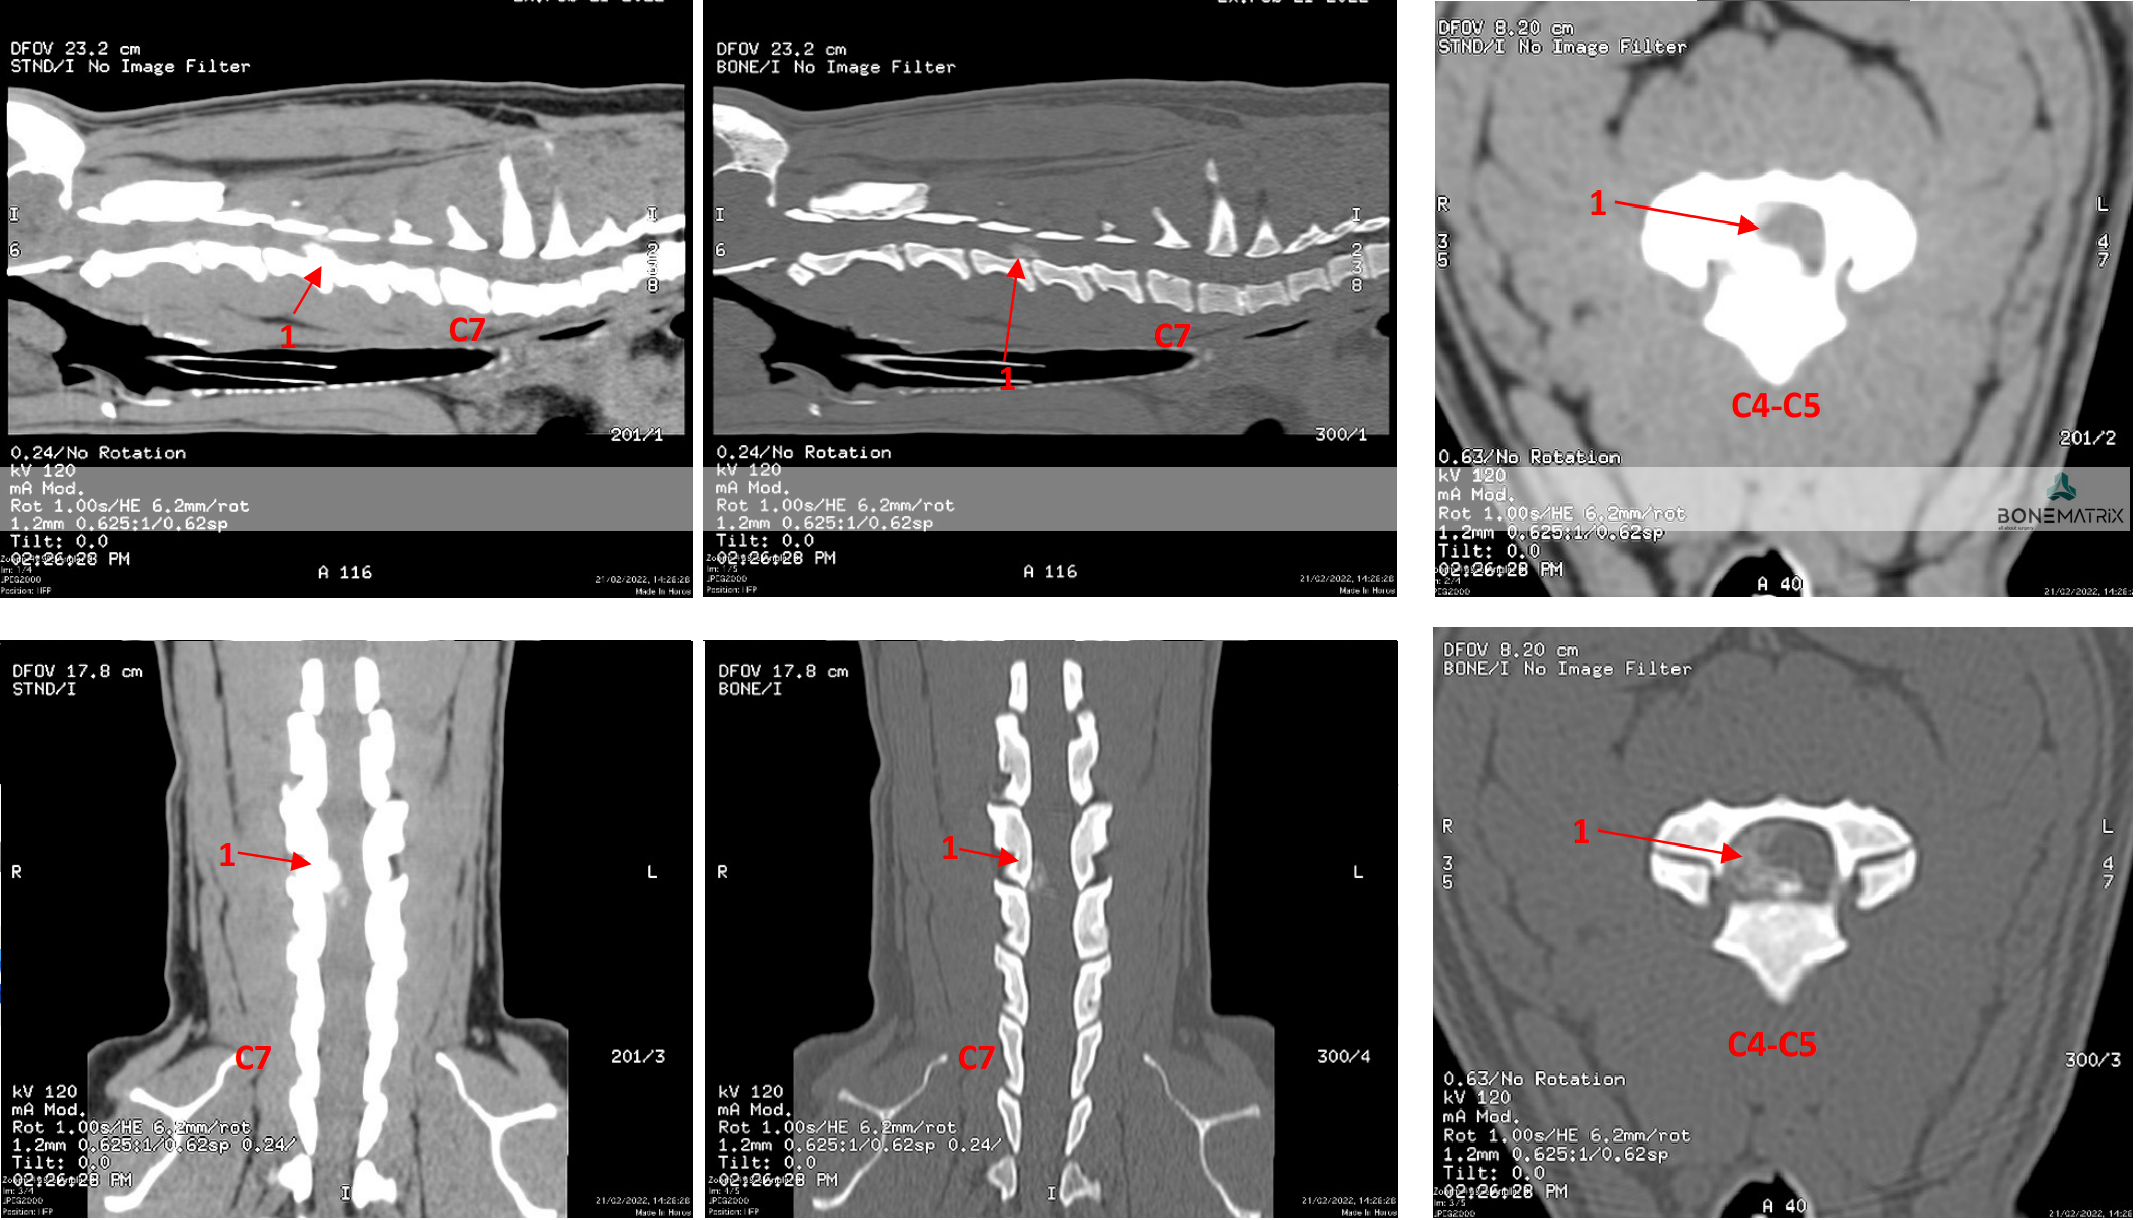

O síndrome de Wobbler também designado por espondilomielopatia cervical é uma causa comum de patologia compressiva de medula em cães de raça grande a gigante.

Em qualquer uma das apresentações da doença existe um efeito compressivo sobre a medula espinal localizado nas vertebras cervicais.

O síndrome de Wobbler pode ter uma apresentação onde a compressão é consequência de uma proliferação óssea a nível das vertebras e outra onde o efeito compressivo advém dos discos intervertebrais.

Como diagnosticar/ Sinais?

Os pacientes que sofrem desta patologia costumam apresentar um quadro crónico progressivo (ao longo de semanas a meses).

Entre os sinais que podem ser exibidos pelo animal estão a hipersensibilidade cervical, a falta de força nos membros, algum grau de claudicação que pode estar associada também com ataxia propriocetiva (hesitação em determinados movimentos por falta de capacidade em perceber a localização do corpo).

Normalmente os sinais são simétricos (apresentados na mesma medida no lado direito e esquerdo do corpo) contudo existem quadros de apresentação assimétrica também.

O diagnóstico é realizado com base em técnicas de imagem avançada (TAC ou RM).

Qual o tratamento indicado?

O tratamento aconselhado para a resolução destes casos é a descompressão medular por meio da realização de uma técnica cirúrgica denominada por Ventral Slot.